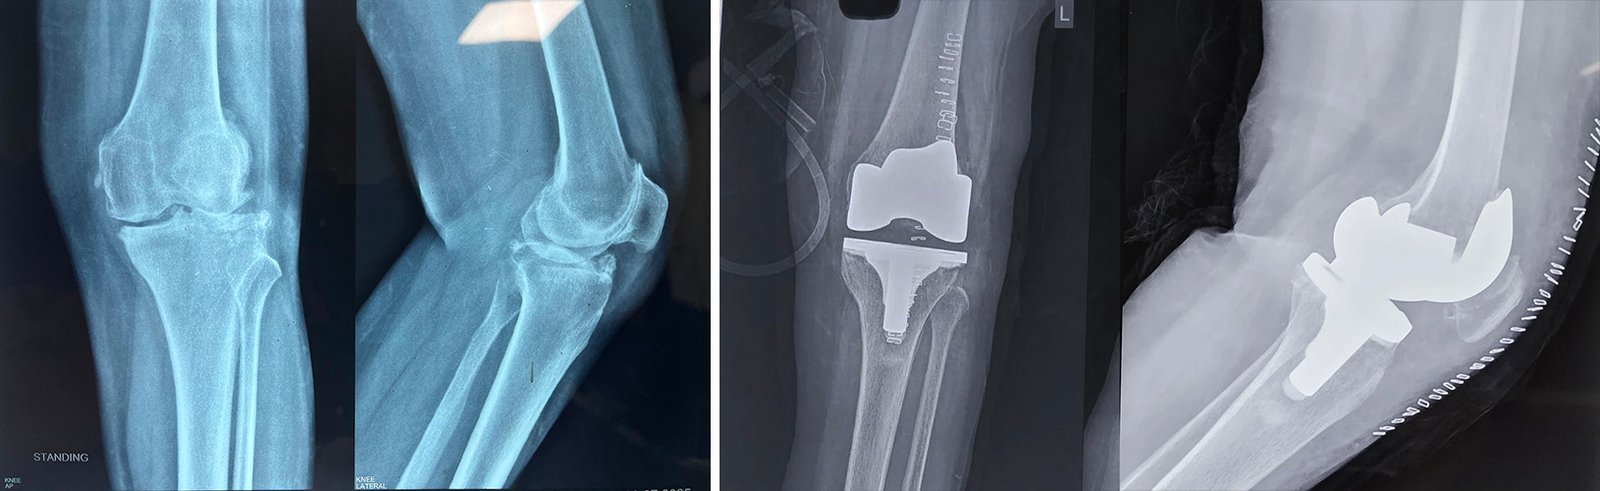

Total Knee Replacement

Are you having pain in your knees? Look no further, because Dr. Sanyal is the best choice for you. He specialises in total knee replacement surgery, offering you a solution to regain your mobility and live pain-free.